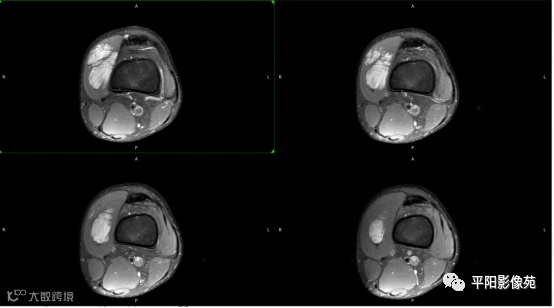

影像表现:

左膝关节股内侧肌内见多房样短T1长T2信号,内可见分隔,增强扫描明显强化,分隔未见明显强化,病灶局部与股骨远端分界不清。

MRI表现:好发于下肢, 较大病灶多为与肢体长轴一致的梭形, 边缘不清, 较小病灶呈类圆形, 边缘较清;②T1WI呈等或稍高信号, 病灶内部或边缘可见线条状或花边状高信号灶, 类似于皮下脂肪信号, T2WI上为明显高信号, 为本病特征性MRI表现;③病灶内静脉石及血管流空影为又一特征MRI表现;④GD-DTPA增强, 病灶明显强化, 其内低信号间隔无强化;⑤可见骨外形改变, 骨质增生及骨质吸收等表现。